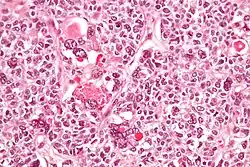

Micrograph of a juvenile granulosa cell tumour with hyaline globules. H&E stain.

Juvenile granulosa cell tumors can be distinguished from adult granulosa cell tumors on histology by their abundant, eosinophilic cytoplasm; primitive, highly mitotic nuclei in polygonal cells; and disorganized follicles.[12][13]